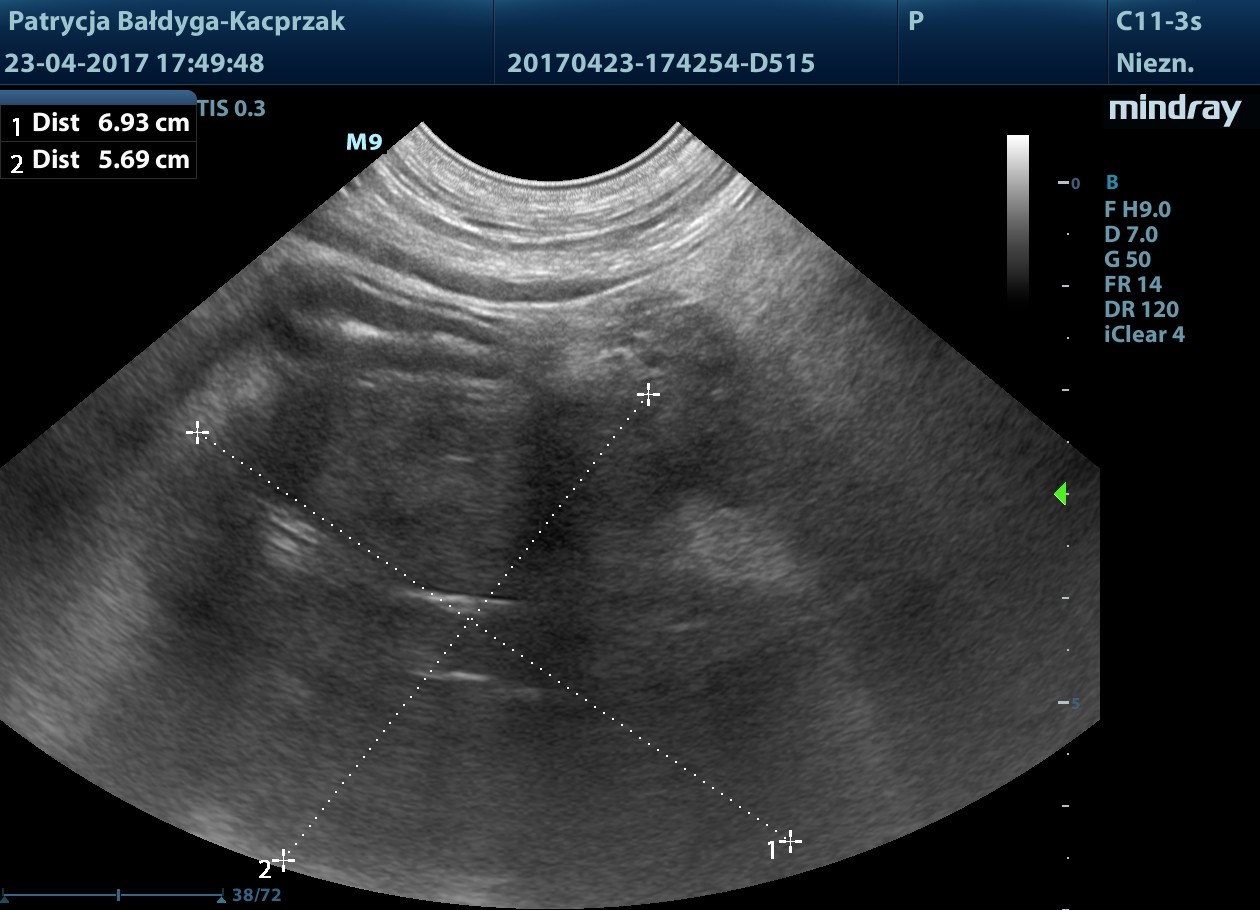

Kwiecień

Guz trzustki powiększył się

W płatach prawych wątroby widoczne nowe ogniska hiperechogenne, okrągłe ok. 13-31 mm, podejrzenie zmian metastatycznych

pod pęcherzykiem żółciowym zmiana ok 4,5 cm z drobnymi obszarami hiperechogennymi, jak zwłóknieniowymi/mineralizacyjnymi, gazem?

obrys 1- tu lekki cień akustyczny świadczący o twardości zmiany, obrys 2- tu artefakt rewerberacji, mogący sugerować obecność pęcherzyków gazu